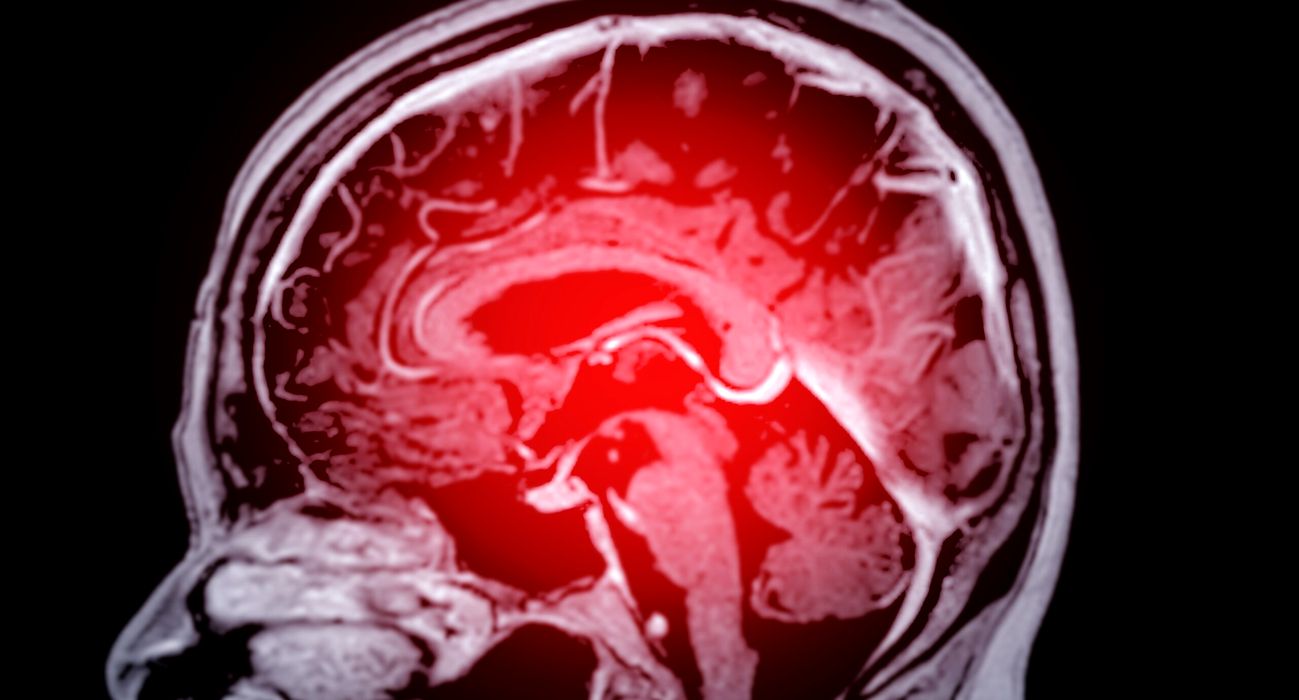

Un semnal ascuns în pulsul uman ar putea semnala un declin cognitiv viitor

Variațiile ușoare din ritmul cardiac al unei persoane ar putea oferi indicii despre probabilitatea apariției unui declin cognitiv în viitor, potrivit unui nou studiu – oferind, astfel, o posibilă metodă de testare rapidă și simplă […]